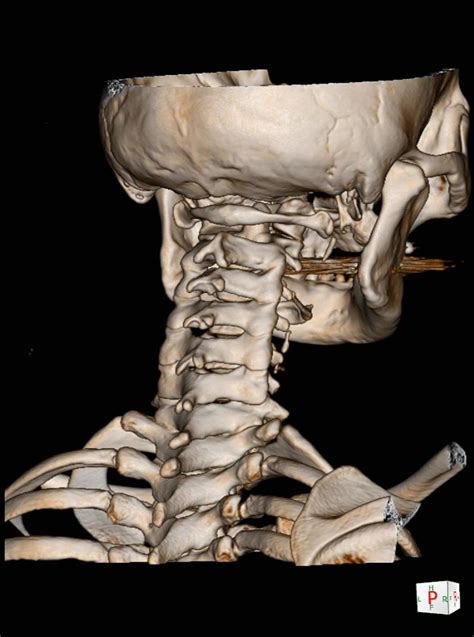

• 3D Reconstruction: This involves generating three-dimensional images of the spine, which can be particularly useful for surgical planning.

These advanced techniques provide more detailed and accurate information, aiding in the diagnosis and treatment of complex spinal conditions.